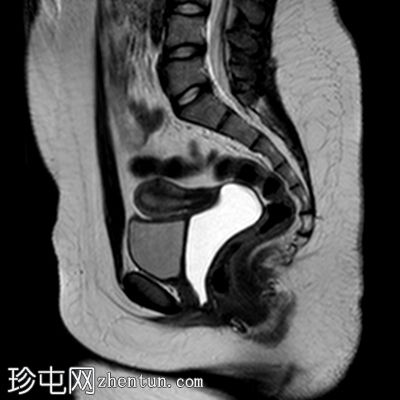

轴位 T1加权像

脂肪抑制序列

阴道明显扩张,T1加权像呈中高信号,T2加权像呈高信号,耻骨联合下方可见一小局灶性隆起。

右侧卵巢可见一圆形、边界清晰的囊肿,最大轴位径为4.2 x 4.3 cm,T1加权像呈低信号,T2加权像呈高信号。

左侧卵巢大小正常,可见一小出血性囊肿。

盆腔内可见少量游离液体。